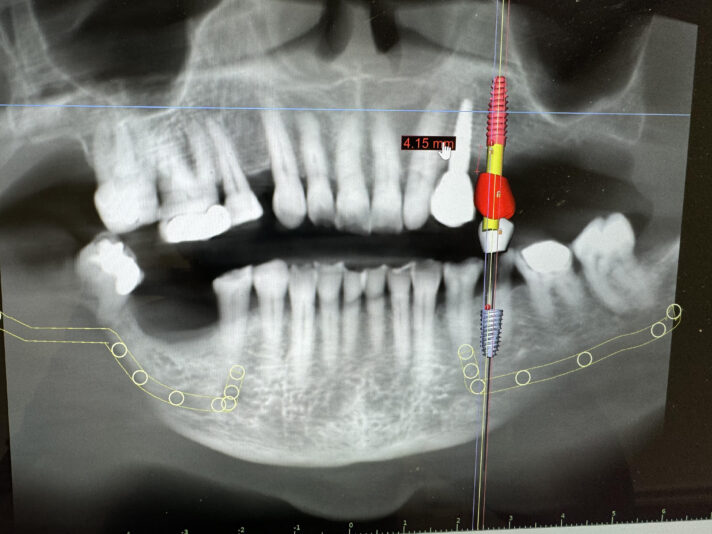

Dr. started the discussion #19 in the forum Implant Tx Planning 2 years ago

Hi,

These are images of a recent scan.

This is 5 months after #19 implant was explanted (failed 2 weeks after placement) and simultaneous grafting was done.

I have currently planned for a Hiossen 4.5x7mm with buccal veneer grafting. This will be placed relatively deep due to ridge atrophy. What are your thoughts on this deep placement…